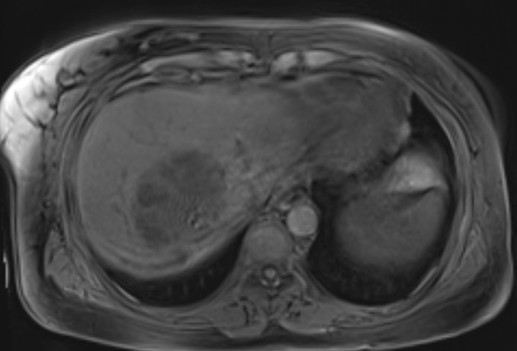

•Axial and coronal T2WI (HASTE sequences): An ~9cm hepatic mass with heterogenous, but predominately hyperintense signal, on T2WI. Associated intrahepatic biliary duct dilation with multiple curvilinear hypointense striations/filling defects.

•Pre and post-contrast T1 fat saturation images: predominately T1 hypointense mass with areas of intrinsic enhancement. Answer: Intraductal papillary neoplasm of the bile duct (IPNB)